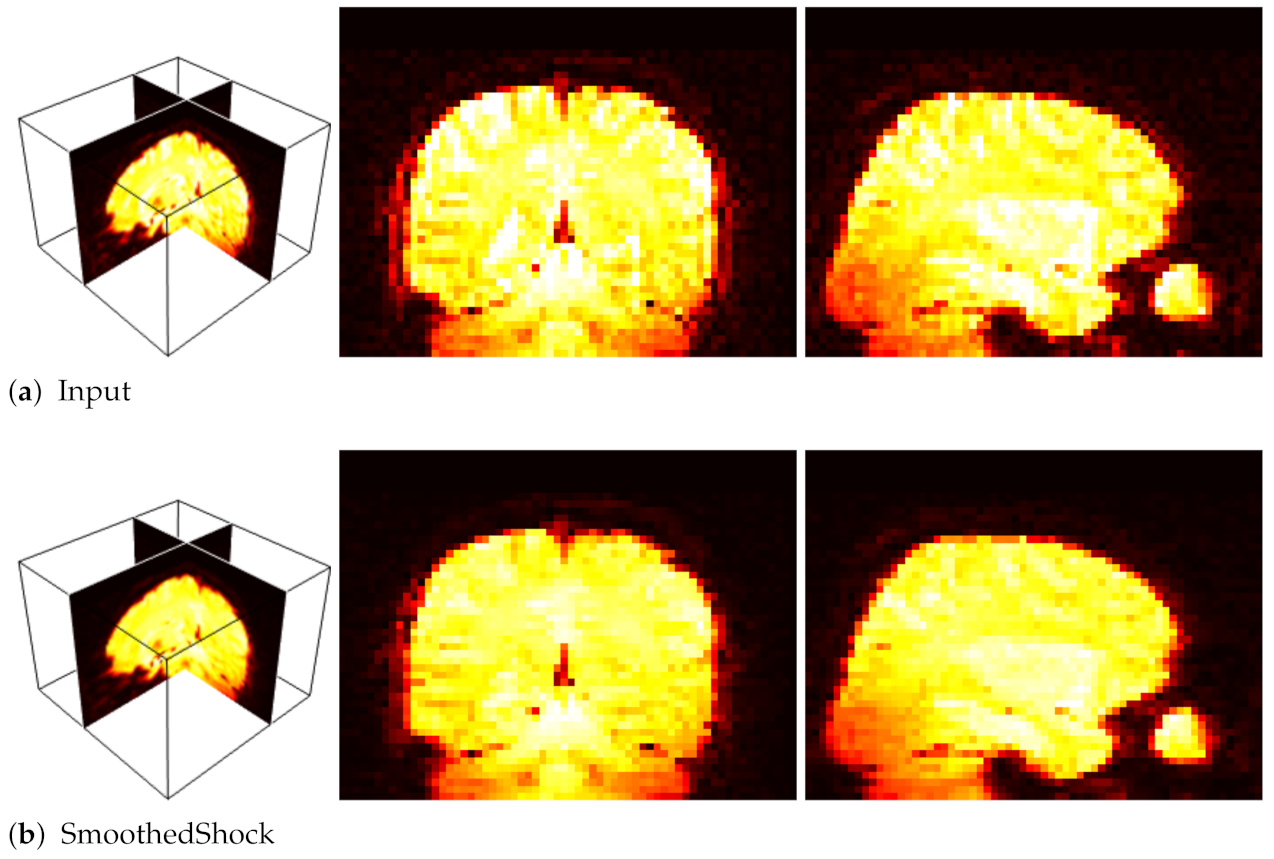

In [7], we showed that our smoothed shock filter can be applied as an efficient pre-processing step for the classification of fMRI volumes. The application was to recognize brain activities from those images, and especially pleasure and disgust. In this context, fMRI scans were acquired while subjects were exposed to pleasant, neutral and disgusting pictures. Then, a classification system based on self-organizing maps was used [31,32] for the classification.

Our objective was to study the impact of smoothed shock filtering on the 3D images for a better recognition. To do so, we compared our filter with a standard fMRI pre-processing algorithm, FLIRT [33,34] and with related works. Table 2 exposes the numerical evaluation conducted with 10 fMRI sequences. Moreover, Figure 12 presents an example of fMRI volume processed with our filter, which smoothes homogeneous regions while preserving important patterns of brain activities.

Figure 12.

Filtering fMRI data: 3D view (left); and selected X and Y slices (right).